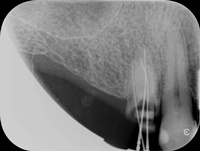

Pacjentka zgłosiła się z bólem. Kilka miesięcy wcześniej leczona kanałowo lewa dolna szóstka. Ząb wrażliwy na nagryzanie. Podjęto decyzję o ponownym przeleczeniu kanałów korzeniowych. Zamknięto perforację przy wejściu do dalszego kanału, usunięto złamaną igłę lentulo z dalszego kanału, udrożniono mezjalne kanały, aż do perforacji korzenia w policzkowym bliższym kanale. Wypełniono dalszy kanał gutaperką, bliższe kanały wypełniono MTA. Ząb do obserwacji, najprawdopodobniej będzie wykonana resekcja wierzchołków bliższego korzenia, na poziomie perforacji.

Reendo 46.